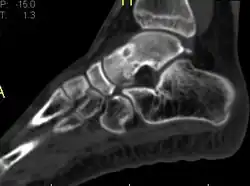

Type Name Sub-type Image

Cancerous Low-grade central osteosarcoma

Osteosarcoma NOS Conventional osteosarcoma

Telangiectatic osteosarcoma

Small cell osteosarcoma

Periosteal osteosarcoma

High-grade surface osteosarcoma

Secondary osteosarcoma